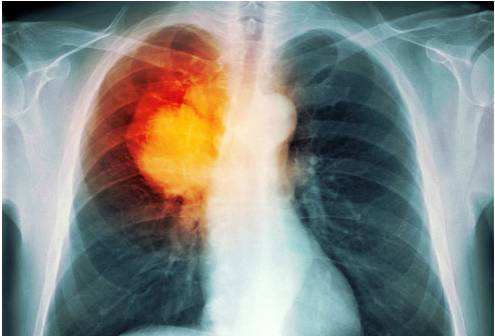

肺癌已成癌魔首恶

据国家癌症中心2018年统计,我国肺癌发病人数和死亡人数已连续10年位居恶性肿瘤之首,每年新发肺癌约78.7万人,因肺癌死亡约63.1万人,每天有1700多人死于肺癌。